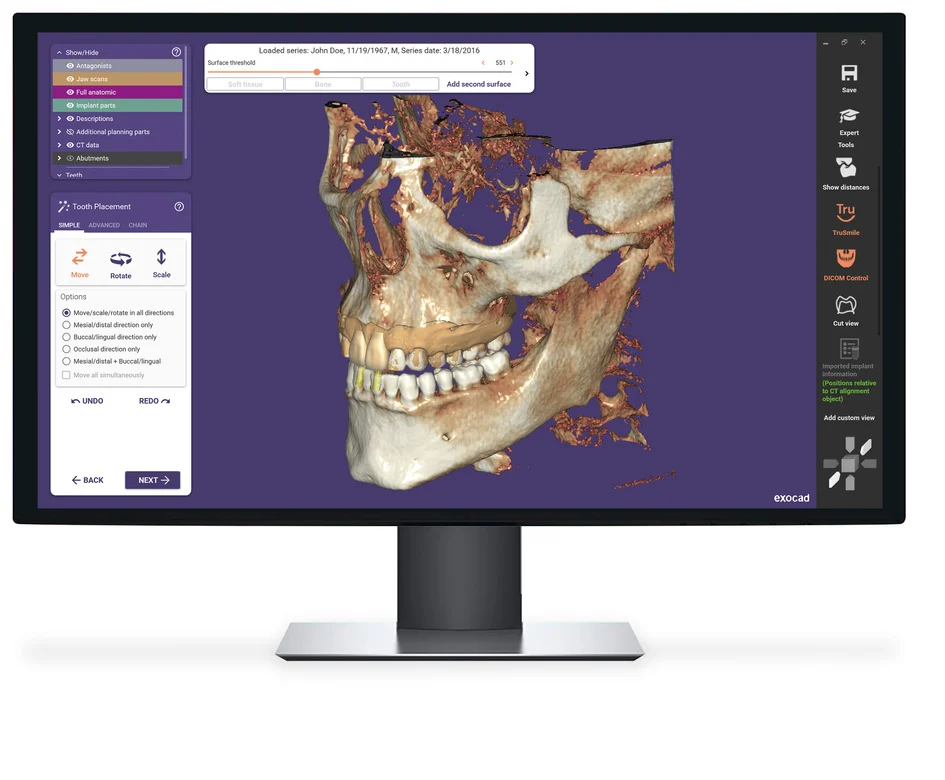

DentalCAD 3.2 Elefsina

Major improvement in automation and integration, better visualization, and improved pre-operative treatment planning!